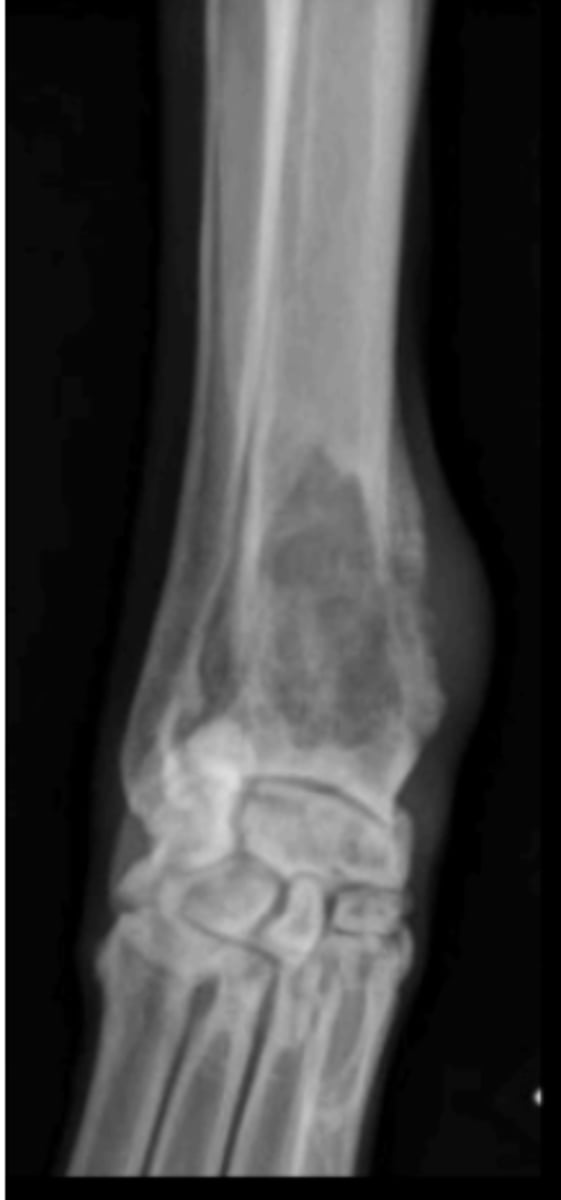

Primary bone tumor

6 y/o dog lame on the limb shown- what kind of tumor is this?